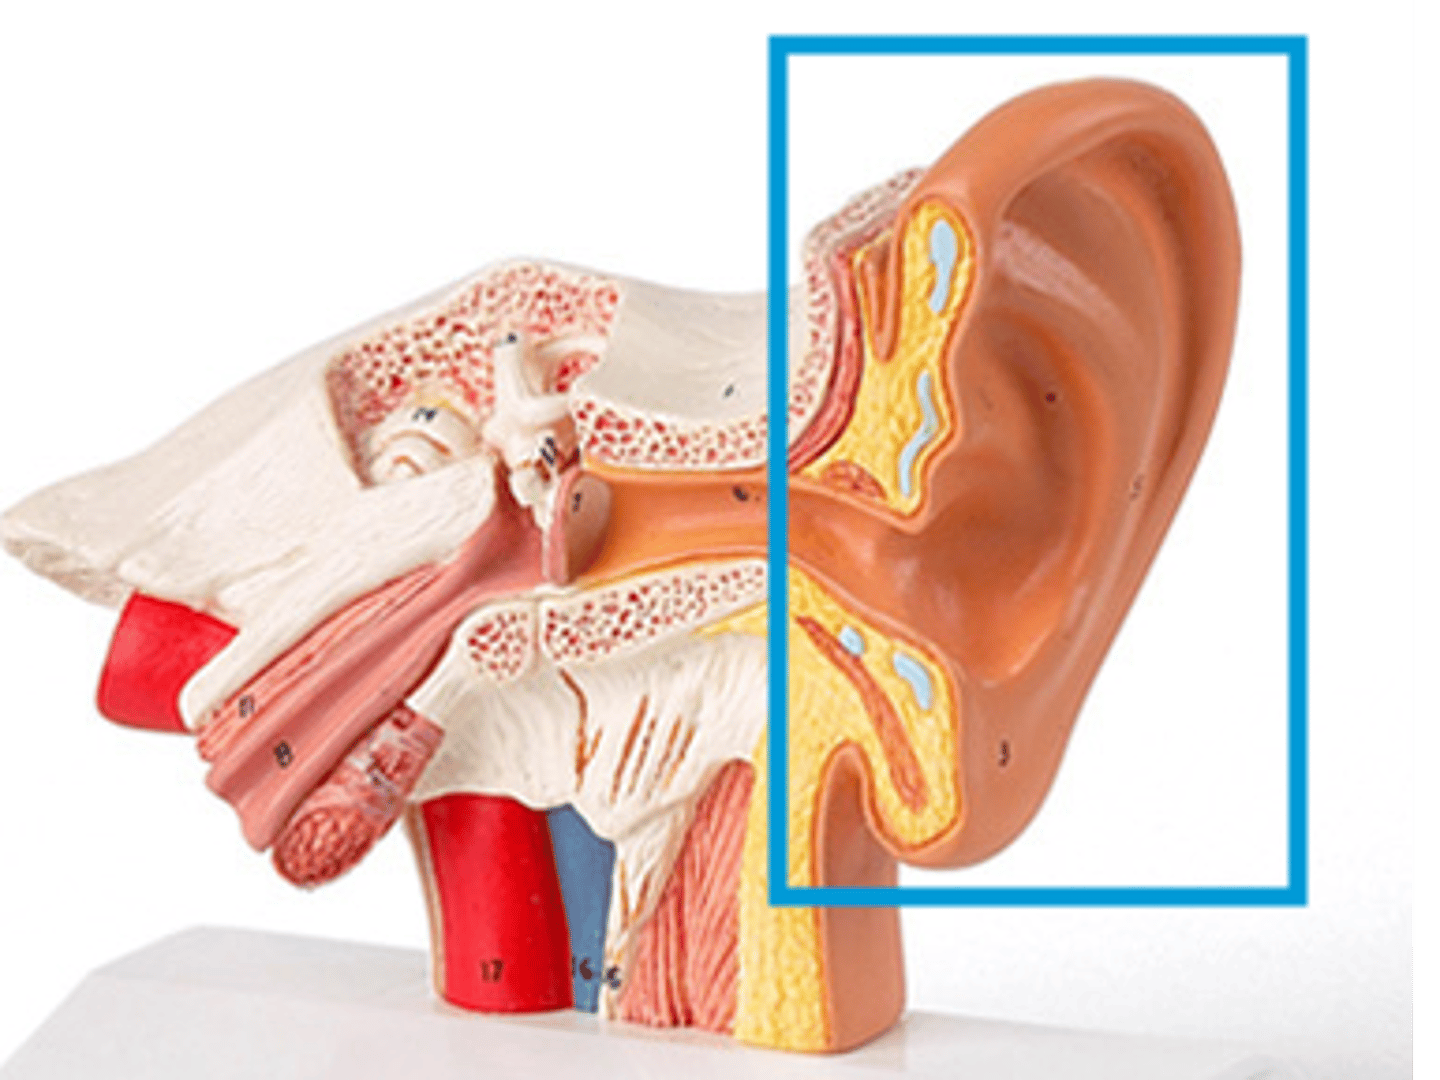

auricle

helix of ear

tragus

EAM

concha of ear